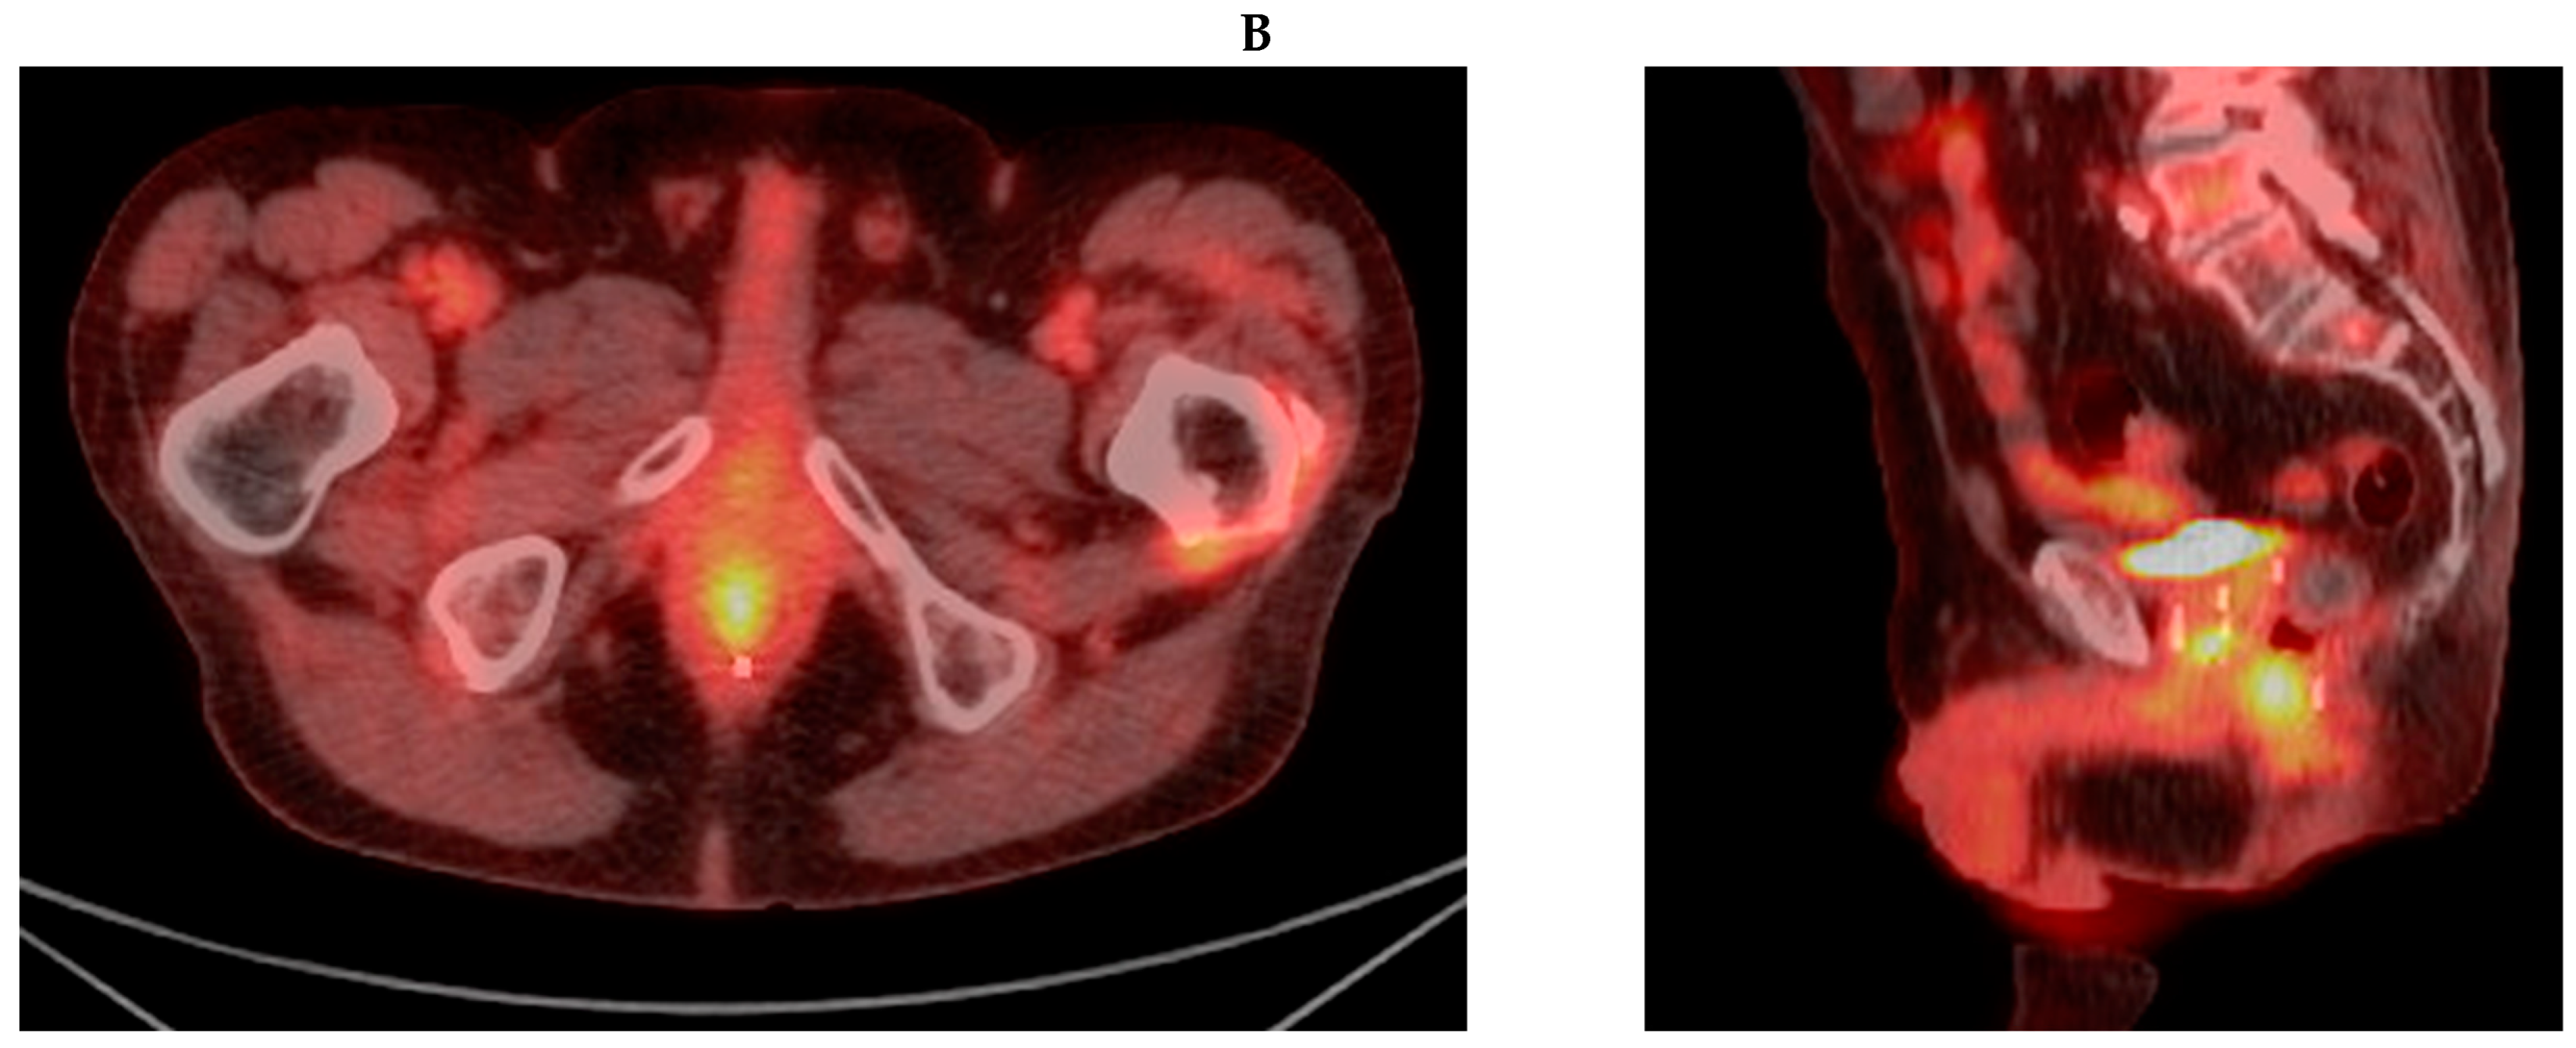

3.2. Case Report 2: Rectal Adenocarcinoma

| Rectal | 2013: -EBRT 81 Gy/45 fx | 2019: -Rectum + LNs 45 Gy/30 fx BID | CR | NED | No POD | No POD | 36 mo |

| Disease | GTV V100% | PTV V100% | Mean Rectal Dose (cGy) | Mean Bladder Dose (cGy) | Max Distance of Spacer (cm) |

|---|---|---|---|---|---|

| Rectal | 62% 1 | 73% 2 | 4462.5 | 3957.6 | 1.10 |